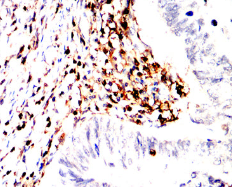

CD45R Mouse Monoclonal antibody[1A5G6]

IHC    1/200 - 1/1000